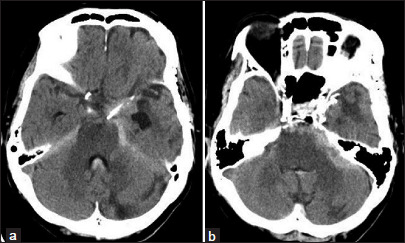

Case description: A 77-year-old woman presented with a sudden headache and computed tomography showed a subarachnoid hemorrhage predominant in the left cerebellopontine angle. Cerebral angiography revealed a saccular aneurysm in the anterior pontine segment of the left AICA. Coil embolization underwent preserving the parent artery. There is no recanalization of the aneurysm at 26 months postoperatively. In this case, hemodynamic stress was suggested to be involved in the development of the aneurysm.